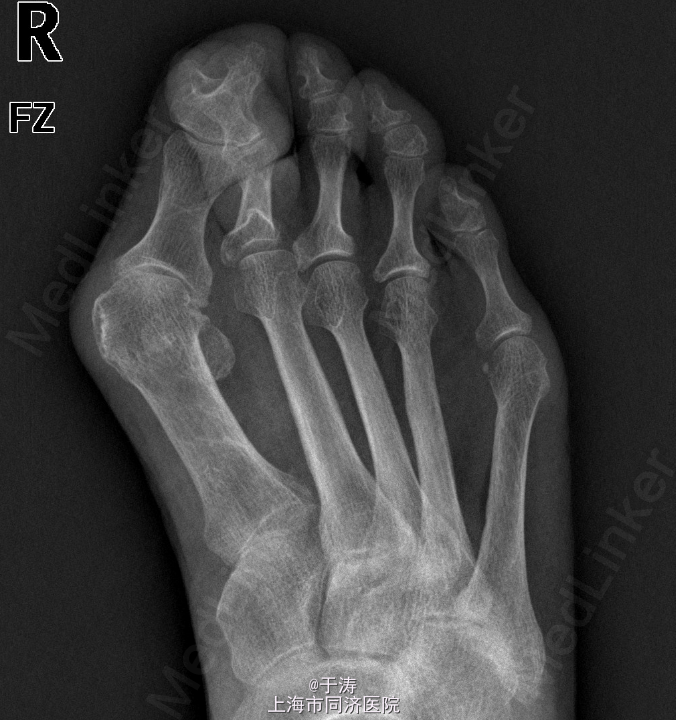

主诉:右足拇外翻畸形6年,加重伴足底疼痛4年。 现病史:患者6年前出现右足拇外翻畸形,疼痛较轻,未予处理。近4年来,患者畸形及疼痛逐渐加重,右足第1、2趾负重时疼痛,保守治疗无效,来我院门诊就诊,以右足拇外翻畸形收治入院。患者自患病以来精神可,纳佳,二便正常,近期无明显消瘦。

查体:右足拇趾呈外翻畸形,右足第1跖骨头内侧可及增生骨赘,无明显红肿,第2趾锤状趾,第2-3跖骨头下方可及胼胝体,压痛阳性,以第2跖骨头下方为甚,第1跖趾关节活动度可,未及明显僵硬,患肢末端血运、感觉尚可。 辅查:X线示第1跖趾关节对位不良,关节间隙狭窄,骨赘形成。

诊断:右足拇外翻,跖痛症,第2趾锤状趾 处理:拇外翻截骨矫形+软组织松解+Akin手术+第2趾近侧趾间关节成形